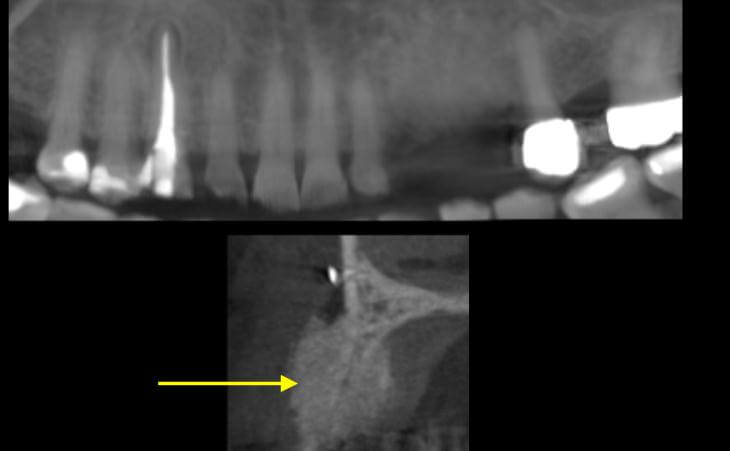

Resorbed Ridge Treatment Before Resorbed Ridge Treatment After

Resorbed Ridge Treatment After -

- thin ridge

thin ridge Pre surgical ct scan showed severely resorbed jaw bone